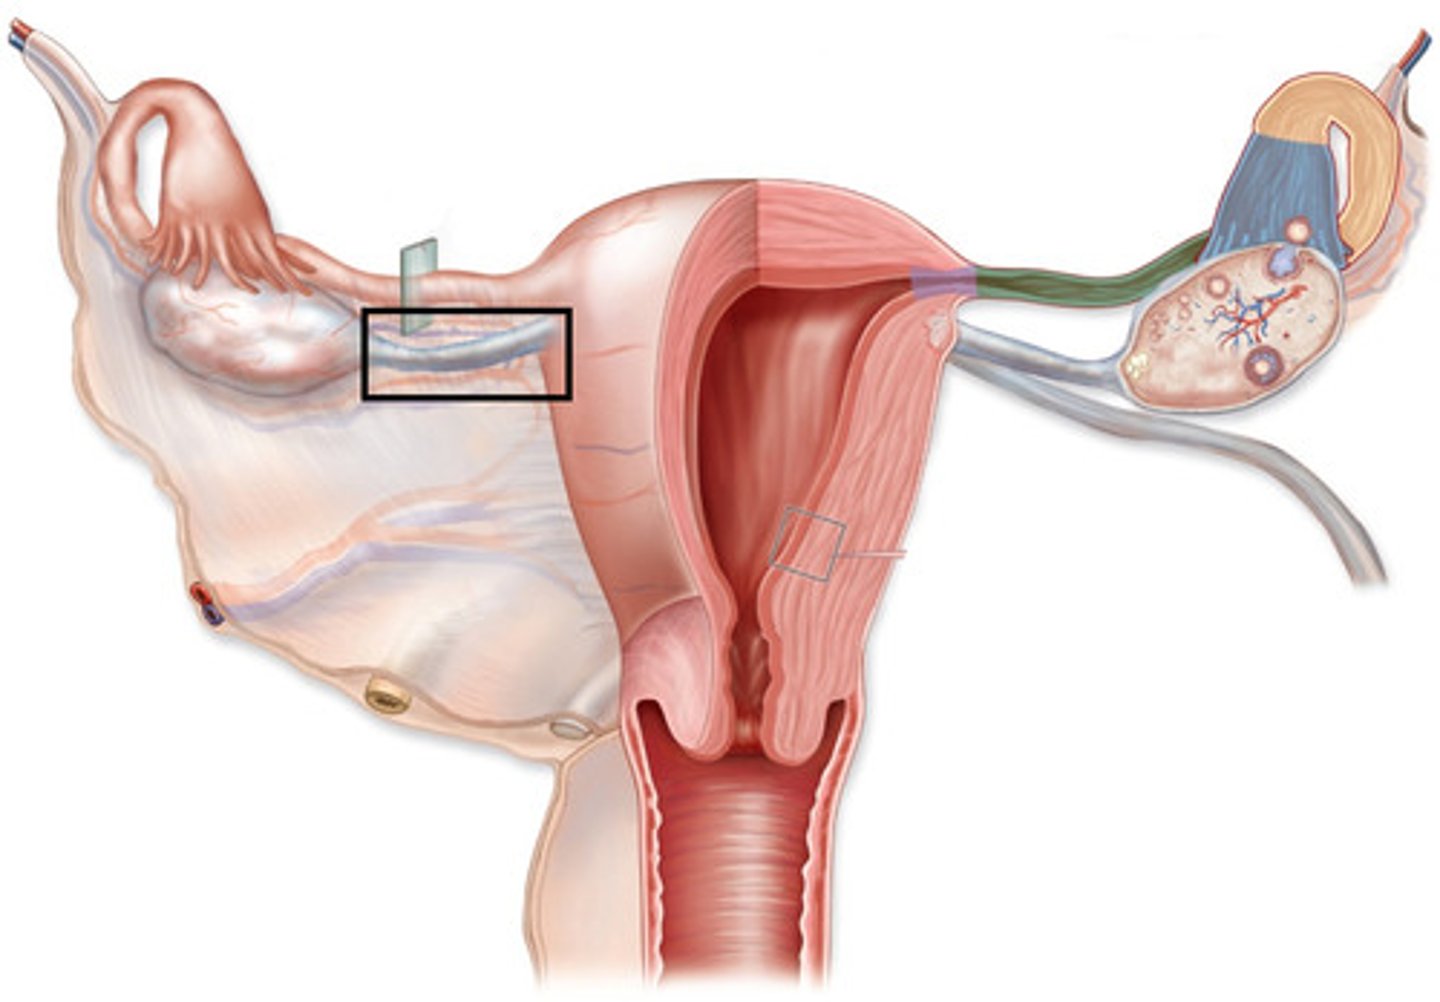

ovaries

primary sex organs of females that produces the gametes and sex hormones

uterine (fallopian) tubes

the uterus

vagina

accessory ducts of the female reproductive system

external genitalia or vulva of the female reproductive system

broad ligament

ligament that hands like a tent from the uterus and uterine tubes

suspensory ligament of ovary

Ligament that contains ovarian vessels

ovarian ligament

ligament that attaches ovary to uterus

uterine tubes (fallopian tubes)

function: receive the ovulated oocyte and provide a site for fertilization

uterus

Female organ of reproduction used to house the developing fetus.

has a fundus, body, isthmus and cervix

perimetrium, myometrium (MUSCLES), endometrium

What are the 3 layers of the uterus from outer to inner?

vagina

birth canal

highly distensible muscular tube that run from the cervix of the uterus to the body exterior at the vestibule